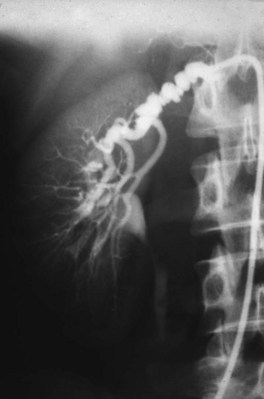

Medial fibroplasia accounts for 75% to 80% of fibrous lesions primarily in women between 25 and 50 years of age. With angiography, arteries demonstrate a “string of beads” in the distal two thirds of the main renal artery and its branches (Fig. 54–43). Multiple microaneurysms can also be appreciated. An estimated 33% demonstrate progression, whereas complete occlusion is rare.

Figure 54–43 Selective right renal angiogram demonstrating medial fibroplasia “beads on a string” in a solitary right kidney.